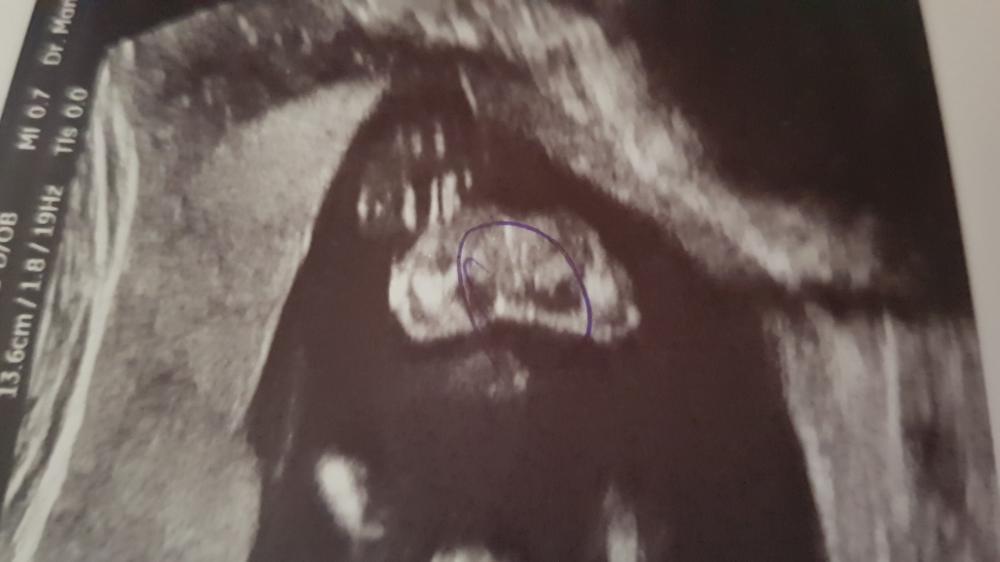

الله يرزقك ماتتمنين